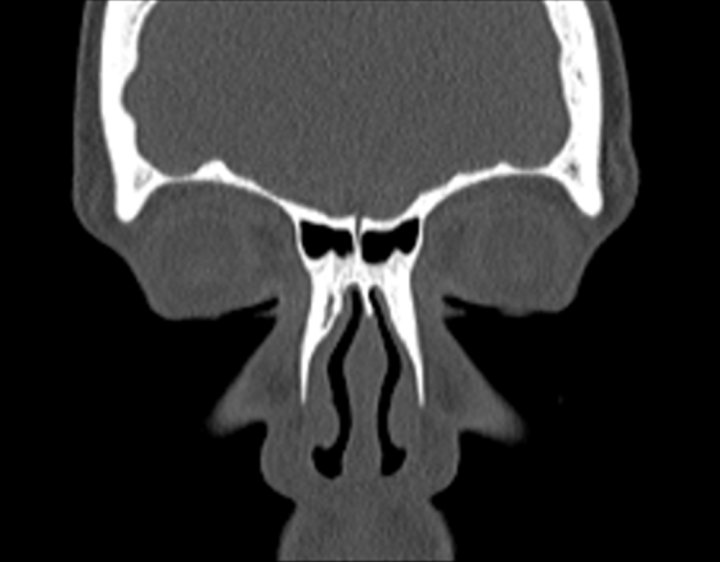

Click any image for labels.